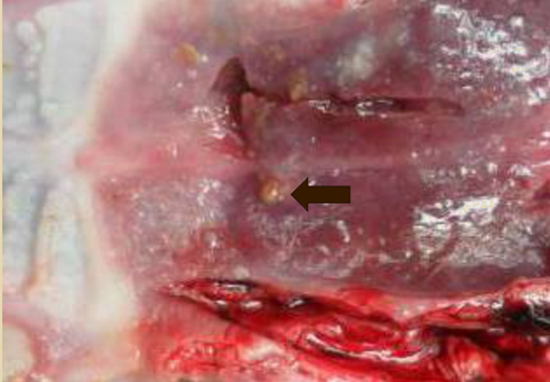

圖4:霉菌毒素中毒癥狀:肝黃凹凸,膽囊萎縮